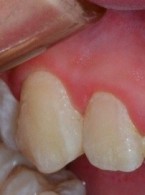

Efektywność nakładek Invisalign® w leczeniu zaawansowanej recesji dziąsłowej – opis przypadku

Zobacz więcej